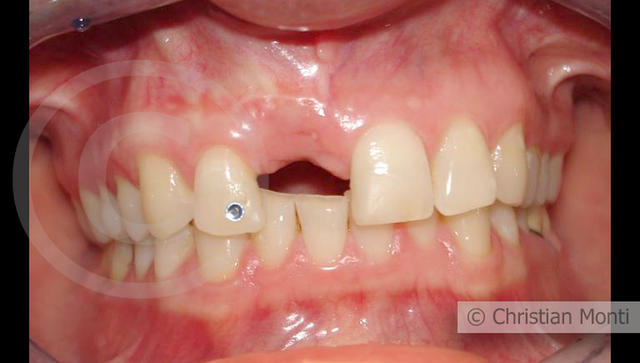

EDENTULIA SINGOLA

Impianto in sostituzione di un incisivo superiore